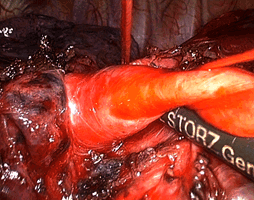

В нашем Центре результаты обследования каждого пациента представляется на клиническом разборе и онкологической комиссии, где после подробного обсуждения выносится окончательное решение. Если оптимальным для больного является хирургическое лечение, операция незамедлительно выполняется торакальными хирургами нашего Центра (рис. 7). В тех случаях, когда вместо операции или после хирургического вмешательства пациенту необходима химиолучевая терапия, мы направляем больного в ведущие онкологические центры нашего города.

Рис. 7. Малоинвазивная радикальная операция при раке легкого - видеоторакоскопическая нижняя лобэктомия слева, выделение легочной артерии.